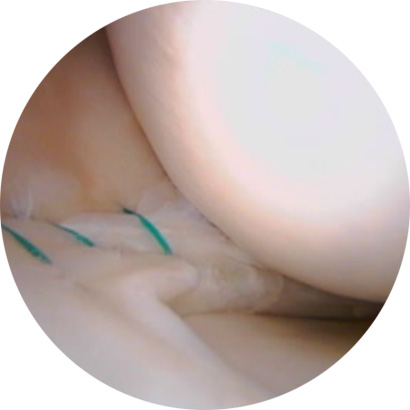

불안정한 반월상연골 부위를 내시경으로 확인하여 파열된 연골판을 꿰맴

약 7mm 정도의 2~3개의 작은 구멍을 무릎 관절 주변에 뚫고

초소형 카메라가 달린 내시경을 삽입한 후 내부를 확인하며

손상된 반월상 연골판을 다듬어줍니다.